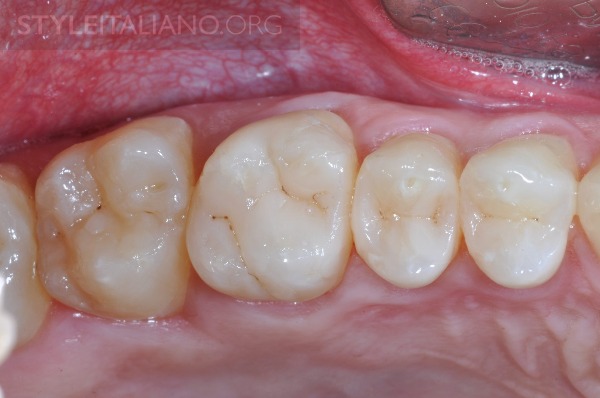

图14 术后六个月,咬合检查

图15 术后6个月,解剖、形态和色泽。

图16 术后6个月,解剖、形态和色泽。